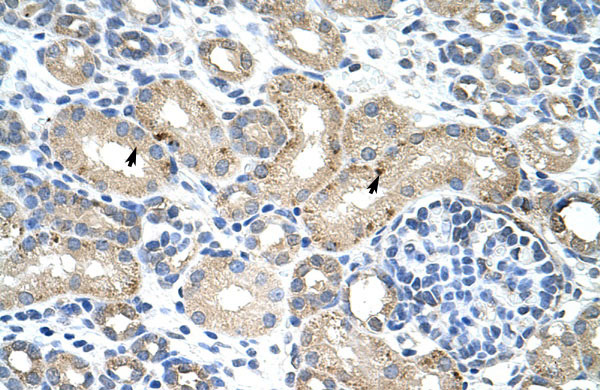

Rabbit Anti-RBM38 Antibody Paraffin Embedded Tissue: Human Kidney Cellular Data: Epithelial cells of renal tubule Antibody Concentration: 4.0-8.0 μg/ml Magnification: 400X